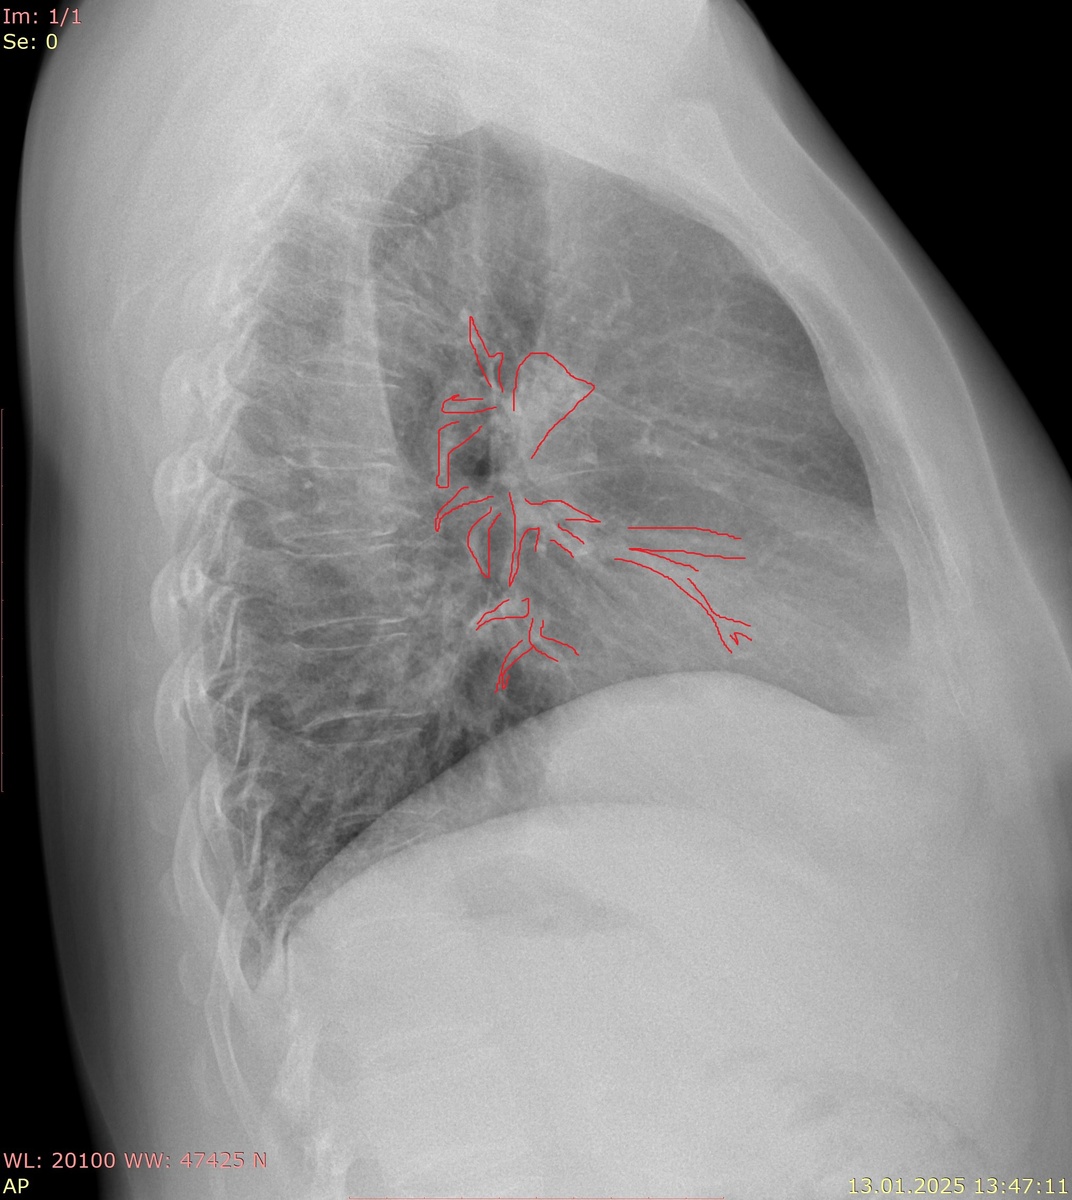

Синим - воздушный столб трахеи, красным - ворота легкого